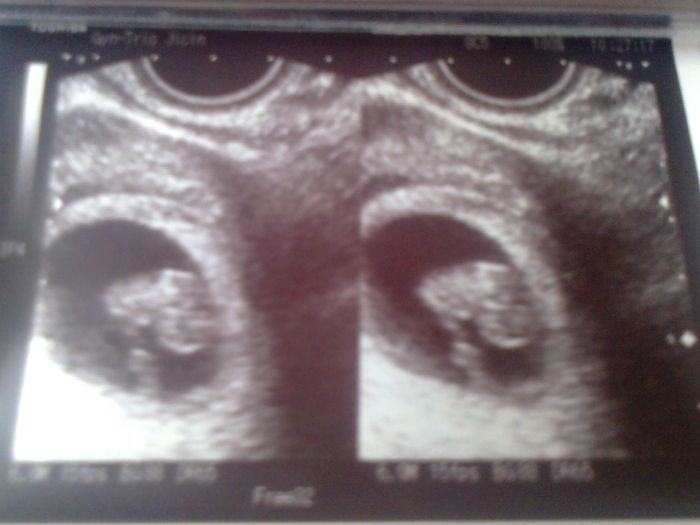

Ahoj holky tak dnešní ultrazvuk super akorát měl pan doktor problém ho změřit nebyl chvilku v klidu. Říkal že to bude nějakej atlet. Průkazku jsem zatím nechtěla ikdyž mi jí chtěl už dát počkám si do dalšího ultrazvuku pro jistotu. Bylo to něco nádherného vidět toho drobečka. Stejně je to krásný dar že se v nás zrodí nový život.